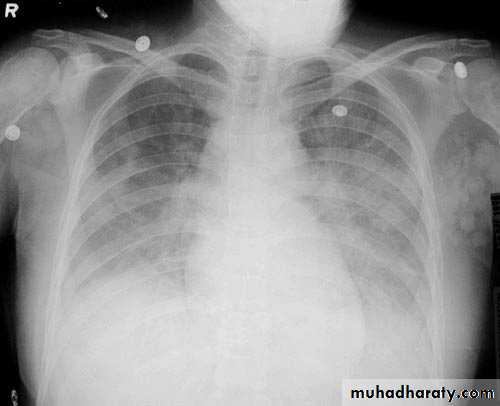

Total lung collapse

chest X-ray